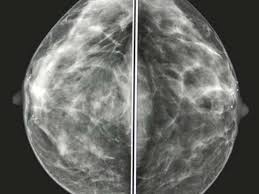

What Do Breast Cancer Feel Like / Understanding Breast Cancer Discover Midwives Previously Our Moment Of Truth - The past several months i have spent in the breast cancer support community have revealed how apologetic and even ridiculous women feel when discussing beauty, sexual desire and pleasure.. Reiland, a breast surgeon with avera medical group comprehensive breast care, advocates for annual mammograms along with clinical breast exams. Cancerous lumps that can be felt from the outside of your body can appear in the breast. Bumps that are cancerous are typically large, hard, painless to the touch and appear spontaneously. Ilc doesn't always form a lump, but women who have it may notice a thick or full area that doesn't feel like the rest of the breast. Learn vocabulary, terms and more with flashcards, games and other study tools.

It felt like a rock in my breast. What do lumps in my breast mean? Breast cancer lumps are usually very hard and are often irregularly shaped. The triple negative breast cancer foundation supports procedures like mammograms to detect breast cancer. Breast cancer lumps are very hard, and they often feel like a bb or a marble, but sometimes they can be difficult to feel. Symptoms of breast cancer are frequent migraines, nausea, your breast become swollen and you can feel it taking a toll on your body. They might be irregularly shaped. As the tumor grows, a person may be able to feel a lump. Ilc doesn't always form a lump, but women who have it may notice a thick or full area that doesn't feel like the rest of the breast. Often, a cancerous lump cannot be moved around in the breast, and pressing on the area doesn't usually. The african american men with breast cancer typically have a lower chance of recovery. Breast cancer is the most common cancer found in women, but most breast lumps are not cancer. Young girls cannot be educated sufficiently about breast cancer through posters and pictures.